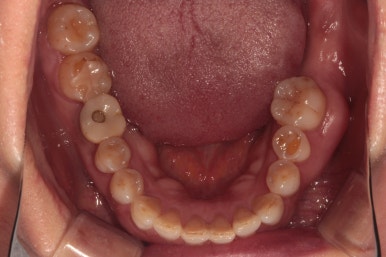

왼쪽 : 위턱, 오른쪽 : 아래턱

마지막으로 위턱 아래턱 교합면 사진입니다.

왼쪽: 위턱, 오른쪽: 아래턱

아래의 치료 전과 스크롤을 올리고 내리면서 비교해보시면 확실히 개선된 상태임을 확인하실 수 있어요.

치아가 없던 자리에 자연스러운 흰색의 지르코니아 크라운을 갖는 임플란트가 생겼고,

이차 충치가 있던 금니도 새로이 제작된 지르코니아 크라운으로 잘 사용하고 있으신 상태입니다.

사랑니가 없어져 더욱 개선된 구강위생관리도 확인할 수 있었습니다!